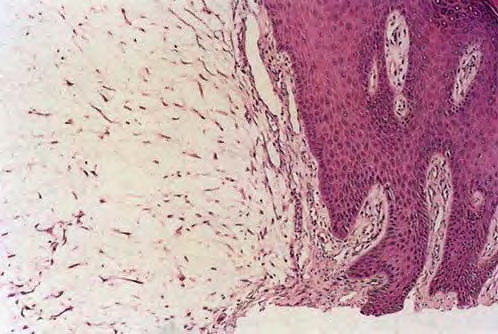

Digital mucous cyst at proximal nail fold.

• Digital mucous cysts are usually solitary, round-to-oval, dome-shaped, firm-to-fluctuant papulonodules from 1-10 mm in diameter that have overlying skin that ranges from very thin to moderately thick.

• The cysts contain a viscous, gelatinous fluid that may be clear or yellow-tinged.

• They most often are found on the dorsolateral aspect of the fingers, intradermally, between the DIP joint and proximal nail fold. Less frequently, they occur between the proximal nail fold and the nail plate, beneath the nail matrix, or in the pulp of the digit.